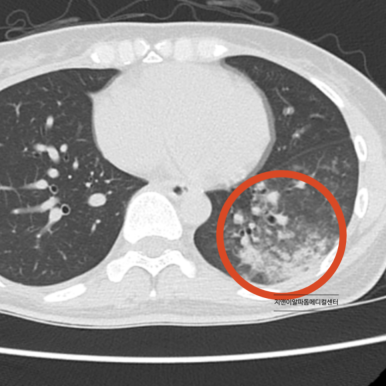

기침 증상으로 내원하셔서 폐렴이 발견된 사례

정상적인 심장 기능은 폐와 전신으로 원활한 혈류를 공급합니다. 하지만 심장 기능이 저하되면 특히 좌심실의 펌프력이 약해지면서 폐에 혈액이 정체되게 됩니다. 이를 폐울혈이라고 하며, 폐 속의 모세혈관과 조직에 과도한 압력이 가해져 체액이 새어 나오게 됩니다.

이러한 울혈과 조직 부종은 폐의 기침 수용체(J-receptor)를 자극하게 되고, 이로 인해 마른기침 또는 숨이 찬 증상이 발생합니다. 더 진행되면 폐포까지 물이 차는 폐부종으로 이어져, 기침은 더욱 심해지고 분홍빛 거품 가래가 동반되기도 합니다.